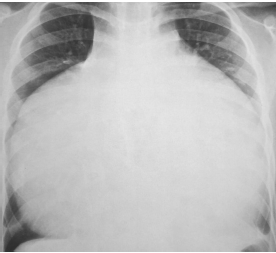

A radiografia de tórax está reproduzida abaixo.

Assinale a opção que mostra o diagnóstico mais provável.